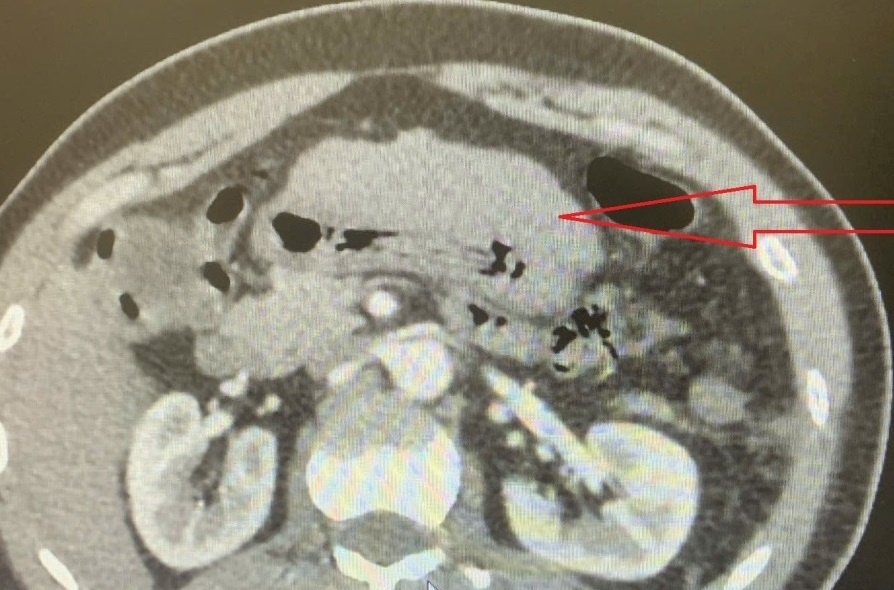

Kết quả siêu âm cho thấy khối u ở gan trái kích thước khoảng 56x58 mm, bờ mất liên tục, có tụ dịch dạng máu ở mặt trước dạ dày và dịch ổ bụng khoảng 50 mm. Ảnh: BVCC.

Kết quả siêu âm cho thấy khối u ở gan trái kích thước khoảng 56x58 mm, bờ mất liên tục, có tụ dịch dạng máu ở mặt trước dạ dày và dịch ổ bụng khoảng 50 mm. Hình ảnh CT-scan sau đó xác nhận khối u gan trái kích thước 58x55 mm, có ngấm thuốc mạnh, xuất hiện động mạch đi vào trung tâm khối, kèm bờ mất liên tục và dấu hiệu chảy máu trong bao gan. Máu lan theo mạc nối nhỏ xuống mặt trước dạ dày (dày khoảng 23 mm), kèm dịch tăng đậm độ dạng máu trong ổ bụng.

Các bác sĩ xác định đây là khối u gan trái đang chảy máu trong bao gan, có nguy cơ vỡ gan và mất máu cấp, đe dọa tính mạng bệnh nhân bất cứ lúc nào.